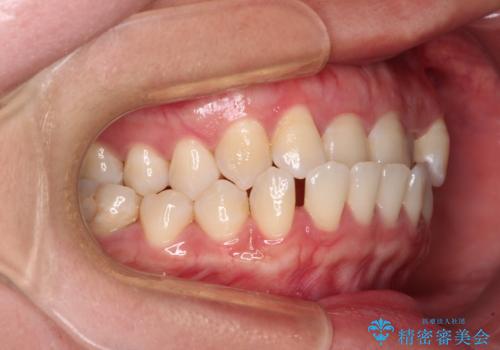

- 全顎的なクロスバイトと反対咬合を気にして来院された患者様です。

骨格的に下顎が前方位にありましたが、歯並びにより下顎が本来の位置よりも前方位に誘導される咬み合わせとなっていました。

上顎歯列および上顎骨が下顎に対して狭小であることが原因であるため、上顎の急速拡大装置を使用して上顎骨を側方に拡大することで反対咬合を改善し、ワイヤー装置で歯列を整えることとしました。